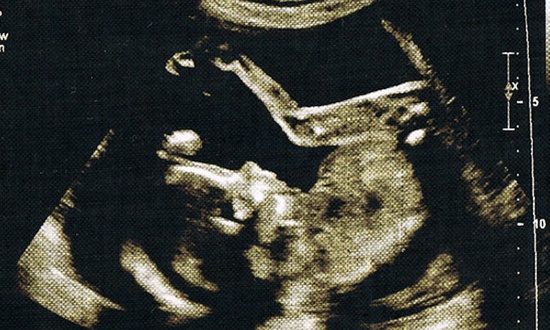

En memoria de un hijo abortado (A Mother's Memorial to Her Aborted Child)